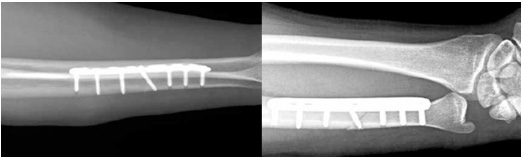

수술시 관절내시경을 통하여 연골상태를 확인하고 삼각섬유연골 파열이 있을 시 봉합술을 같이 시행한 뒤, 척골의 길이를 단축하는 척골단축술을 시행합니다. 단축할 길이가 2mm이하라면 관절내시경(Wafer 술식) 만으로 치료가 가능하나, 2mm이상이라면 관절내시경 만으로는 결과가 좋지 않으며, 통증이 남고 재발하는 경우가 흔합니다.

이때에는 금속판을 이용한 척골 단축술을 시행하여 많은 환자에서 좋은 결과를 보이고 있습니다. 아래 사진은 고식적 방법의 척골 단축술이며 국내 또는 국외에서 많이 시행되고 있는 방법입니다. 4mm 이상의 뼈를 단축할 수 있고, 장점이 많으며 좋은 결과를 보고하고 있으나, 절개부위가 크며 절골술 부위의 불유합이 발생할 수 있다는 단점이 있습니다.

본원에서는 원위 골간단부 척골단축술과 관절내시경 치료를 주로 시행합니다. 절개부위를 최소화 하고 불유합 가능성을 낮추며, 한번의 절개로 삼각섬유연골 봉합까지 같이 시행할 수 있다는 장점이 있습니다.